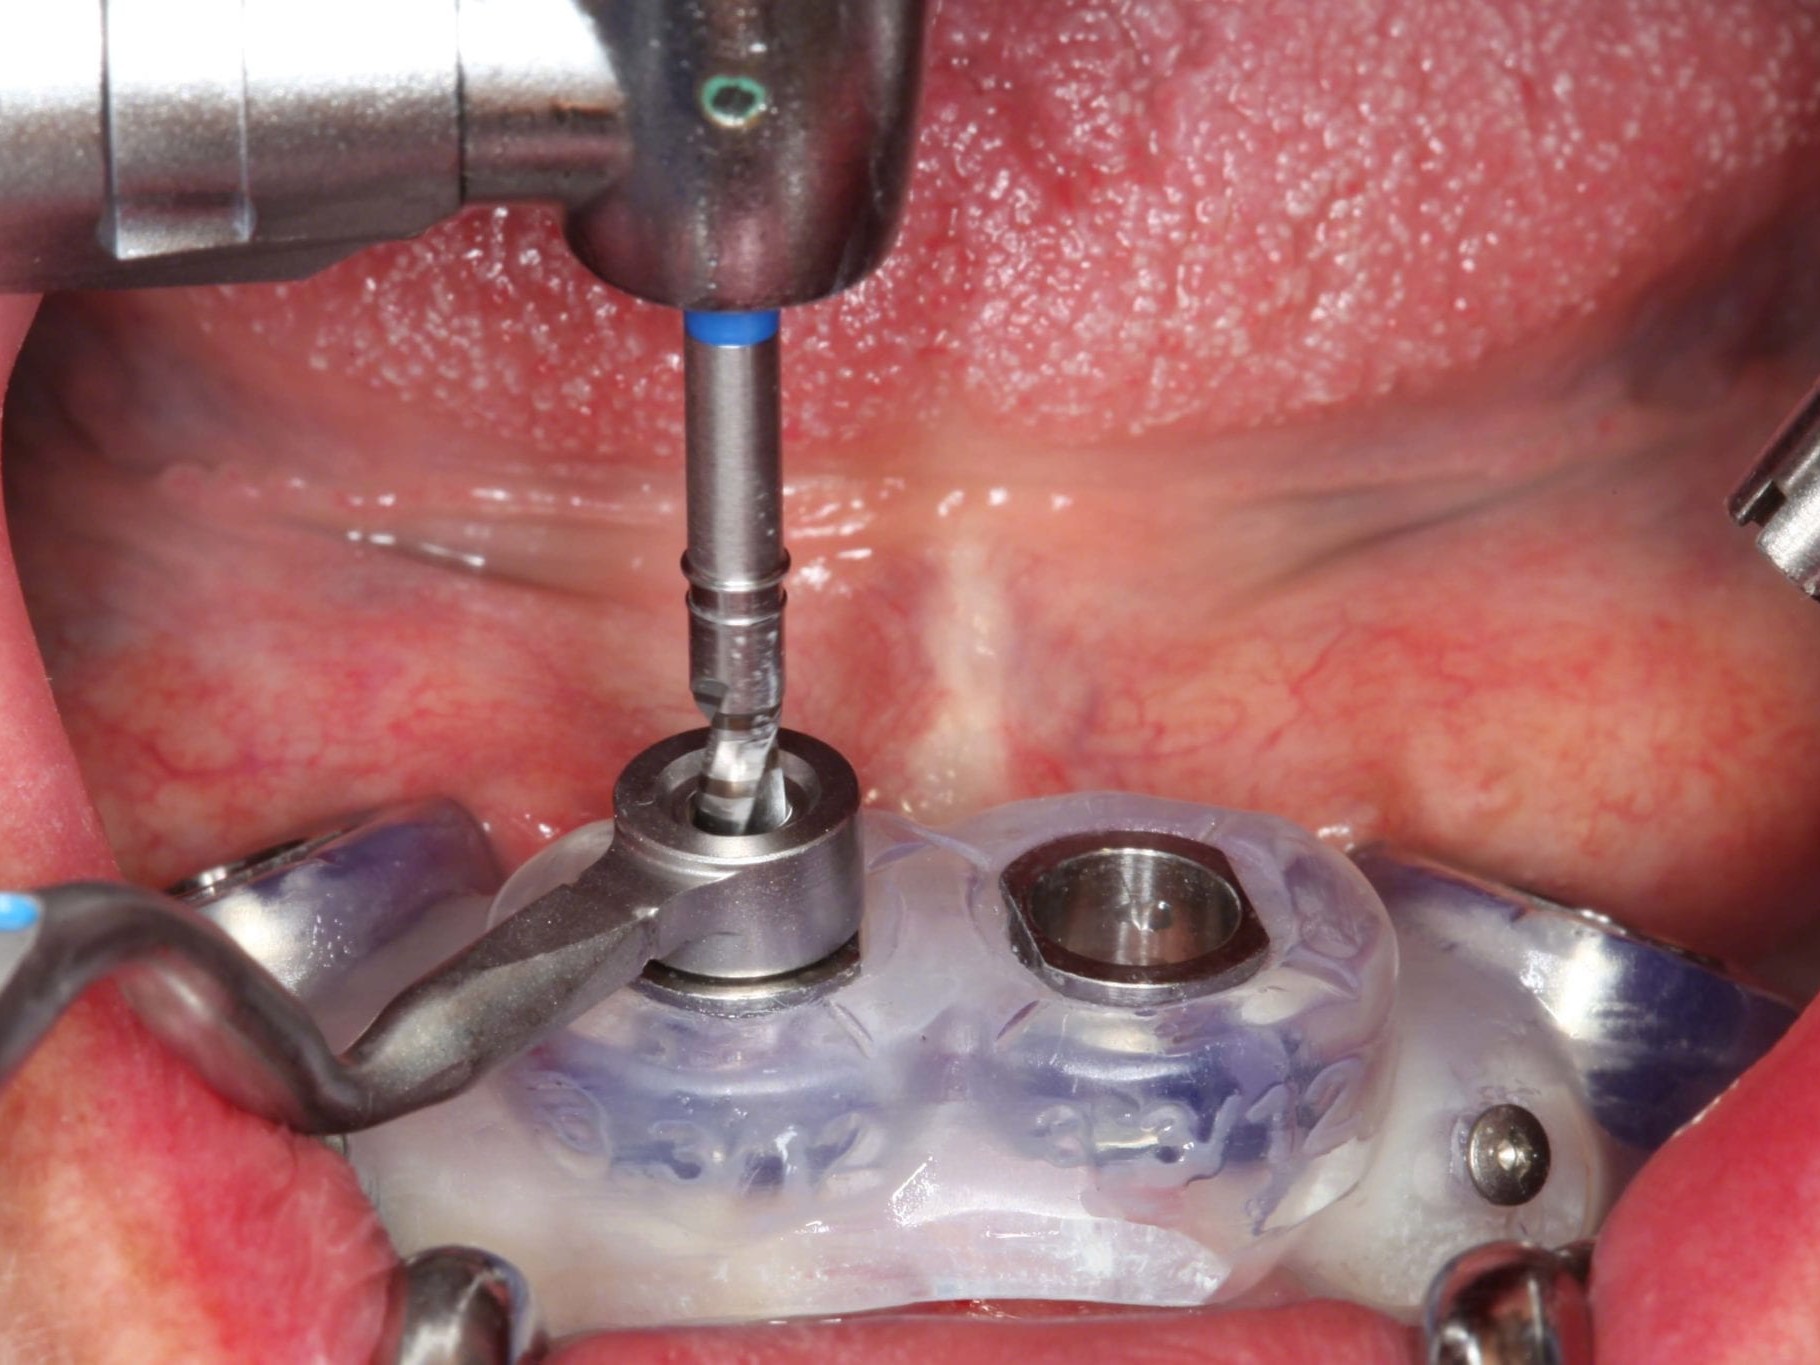

In Lokalanästhesie unter anästhesiologischem Standby mit intravenöser Antibiose mittels Clindamycin 600 mg 2mal/d wurde die Bohrschablone eingesetzt und mit Osteosyntheseschrauben fixiert (Abb. 8). Der Eingriff erfolgte nahezu flapless und somit transgingival. Nun erfolgte die Umsetzung des Straumann Hülse-in-Hülse-Konzeptes. Der Zylinder des Bohrlöffels wird in die an der Bohrschablone fixierten Hülse (Ø 5 mm) in den geplanten Regionen eingeführt. Für jeden Bohrerdurchmesser (Ø 2,2 mm und Ø 2,8 mm) ist ein entsprechender Bohrlöffel erhältlich. Jeder Bohrlöffel besitzt an seinen Enden Zylinder unterschiedlicher Höhe, die entsprechend chirurgischem Protokoll angewendet werden. Es wurden sämtliche Bohrstollen protokollgemäß aufbereitet (Abb. 9-11). Nach der Aufbereitung der Bohrstollen für die angulierten Implantate (Abb. 12-14) wurden die Straumann Bone Level Tapered Implantate (ø 3,3 mm) in regio 035 (Länge 10 mm) und 045 (Länge 12) gesetzt (Abb. 15). Abschließend wurden sämtliche Endpositionen der Implantate in regio 035 und 045 anhand der Lasermarkierungen am Übertragungsteil betreffend ihrer orovestibulären Ausrichtung exakt überprüft (Abb. 16). Nach Entfernung der Einbringhilfen und der Osteosyntheseschrauben konnte die Bohrschablone wieder entnommen werden. In regio 032 und 042 wurden nun die durchmesserreduzierten Straumann NNC (ø 3,3 mm Länge 12 mm) Implantate inseriert (Abb. 17, 18). Bei diesen Implantaten bedurfte es keiner Ausrichtung bezogen auf die orofasziale Ausrichtung. Hier musste die Insertionstiefe bezogen auf das NNC-Implantat beachtet werden (Abb. 19). Die NNC-Implantate wurden mit den entsprechenden Klebebasen versehen (Abb. 20). Danach wurden in regio 035 und 045 auf die Pro Arch Sekundärteile die dazugehörigen Retentionskappen (Abb. 21), die zur Vergrößerung der Oberfläche mit 120 μ Aluminiumoxyd abgestrahlt wurden, eingesetzt. Es erfolgte der typische Naht-Wund-Verschluss mit Einzelknopfnähten. Zum Abschluss erfolgte das prothetische Procedere mit der Eingliederung des Interimszahnersatzes in Okklusion (Abb. 22). Hierfür wurden die Retentionskappen und die Klebebasen mit dem Sofortprovisorium über ein selbsthärtendes fluoreszierendes kaltpolymerisierendes Paste-Paste-Kartuschensystem fixiert, dieser Zahnersatz extraoral versäubert (Abb. 23) und in der Mundhöhle refixiert (Abb. 24). Die Schraubenkanäle wurden mit Kunststoff verschlossen (Abb. 25). Abschließend erfolgte die radiologische Kontrolluntersuchung (Abb. 26).